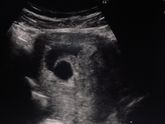

УЗИ

Кто что скажет? врач сказала что эмбриона не видно, почему?

Беременность 4 недели